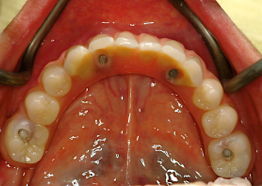

最低4本のインプラントを埋入し、それらを連結し、半日で固定式の仮歯まで入れて審美性、機能性を一日でとりもどせる革新的な治療。

1.従来インプラントは歯茎の中の骨に結合する3〜6ヶ月までは、歯をいれて噛ませることはできないと言われてきましたが、特殊な手術法によりインプラントを埋入し、4本〜6本を連結固定することにより、手術したその日からインプラントで食事を噛んでもらうことができるようになります。

2.歯の形はほぼ天然歯があった時と同じになるので取り外しの義歯に比べて違和感がなく、手入れもインプラントの本数を少なくすることにより、清掃もし易くなっています。